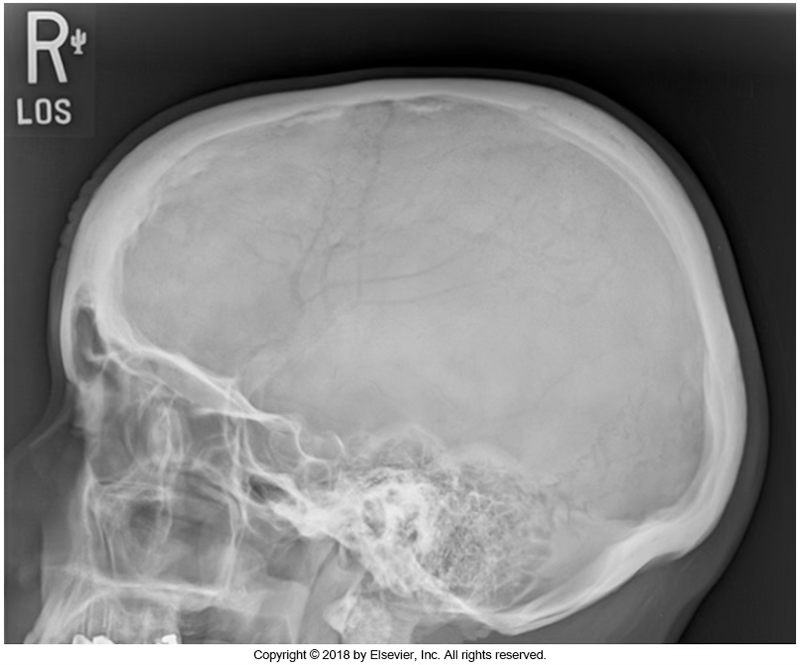

What view is this?

Lateral skull